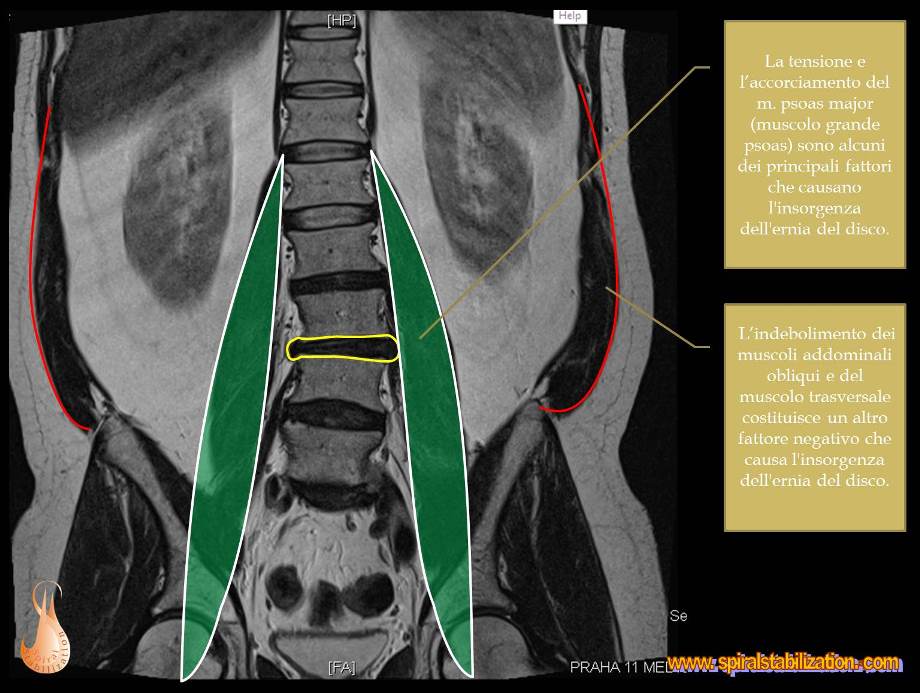

B - 1 - 1 -1

Ernia del disco L3/L4